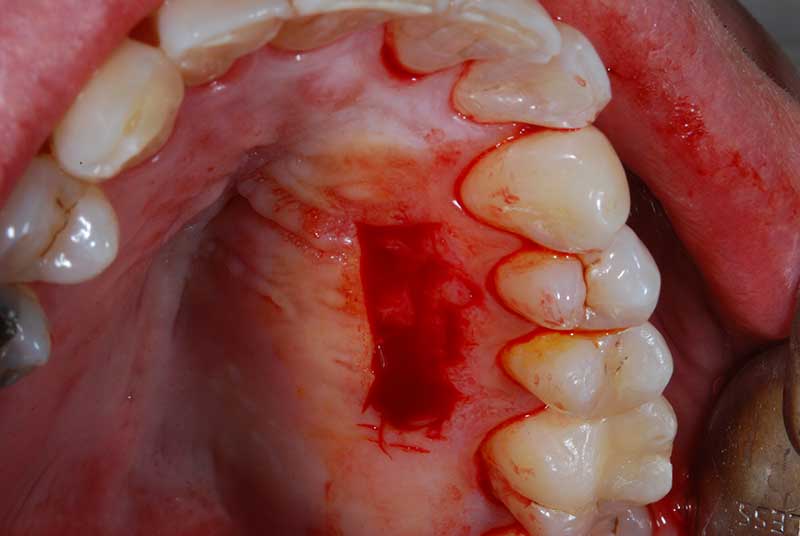

Con protesi fissa superiore e protesi fissa inferiore

I denti irrecuperabili dell'arcata superiore ed inferiore del paziente di anni 65

sono stati sostituiti da 10 impianti, cioè protesi radicolari endo-ossee che sostengono le protesi fisse superiore ed inferiore.